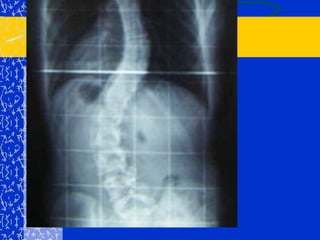

ESCOLIOSISDefinición: (escolios =tortuoso)	Desviación lateral de la columna vertebral  > 5° en el plano frontal.

RADIOLOGIASirve para ver:Localización, número e intensidad de incurvaciones.

Curvas secundarias o compensadoras.

Inclinación de la pelvis.

Dirección del vértice de la curva.

Anomalías de cuerpos vertebrales.

Lesiones vertebrales primarias (tumores).

Grado de madurez del esqueleto.

Cifosis, lordosis o espondilolistesis asociadas.

Medición del  ángulo de incurvación.